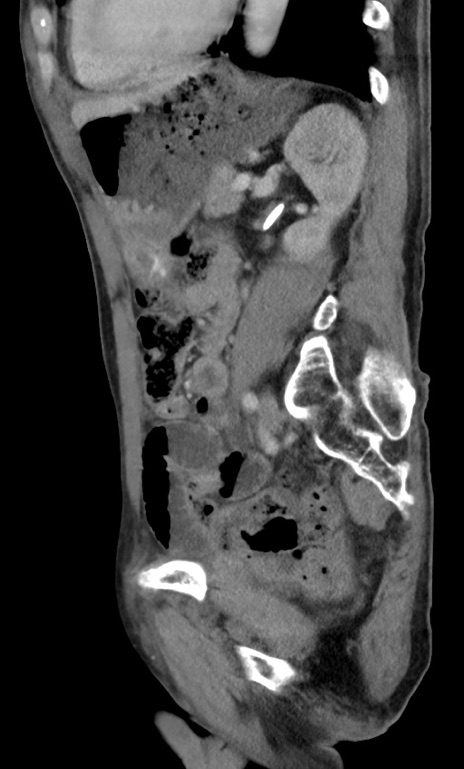

症例3(矢状断像)

【症例】 70歳代男性

【主訴】右鼠径部腫瘤、疼痛

【現病歴】本日朝より上記主訴あり、受診。

【既往歴】膀胱癌にて膀胱全摘、両側尿管皮膚瘻

【データ】WBC 5600、CRP 0.56